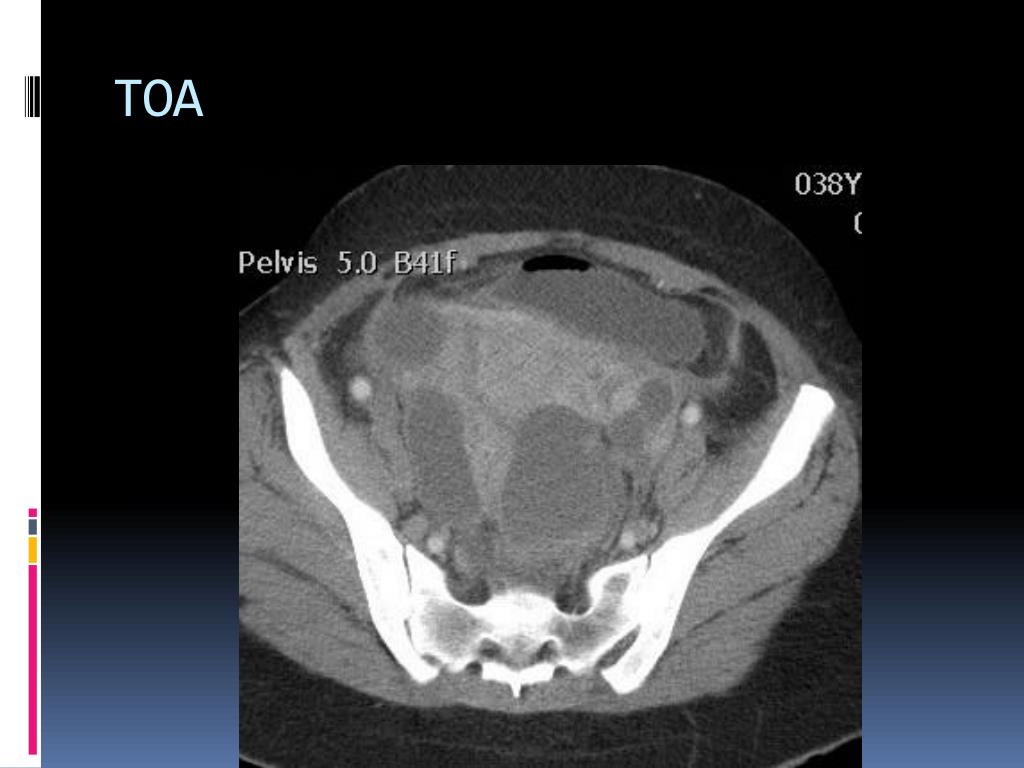

11. TOA

4. 13 f